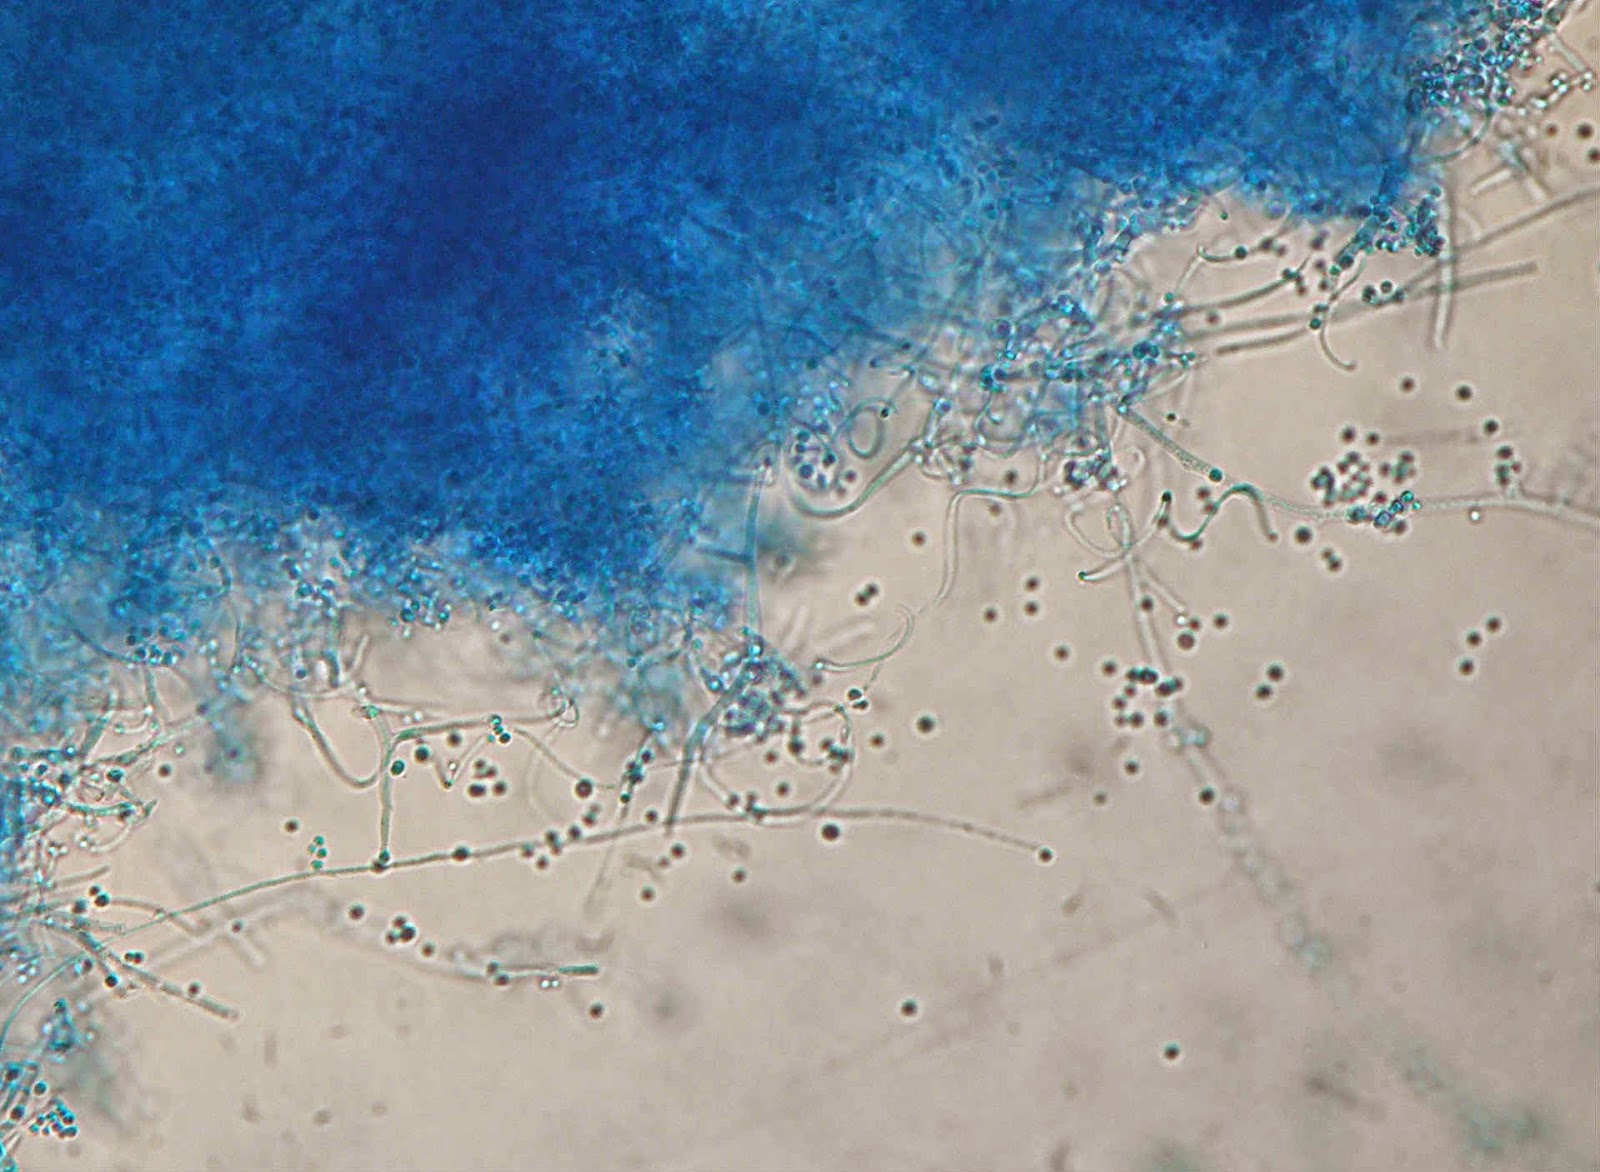

Aspeto microscópico tipico: microconideos abundantes e arredondados dispostos fazendo lembrar cachos de uva.

Hifas espiraladas (azul lactofenol).